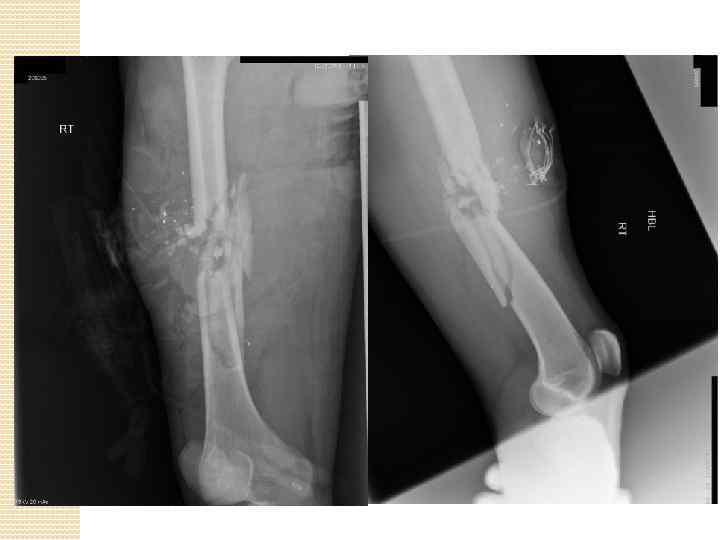

Огнестрельное ранение голени